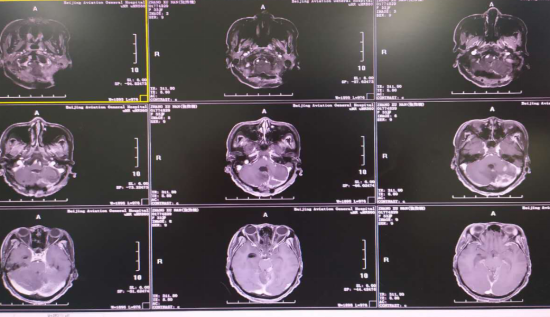

核磁增强:小脑-脑干多发脓肿、感染性血肿

呼吸衰竭、循环衰竭、下丘脑功能衰竭、代谢紊乱、深昏迷植物状态、全脑室化脓、小脑-脑干旁多发脓肿.......每一个都如一座大山般难以逾越。

傅继弟教授与组内医生进行了多次讨论,患者目前生命体征已经平稳,那么是维持目前的方案,还是进一步激进的手术?颅内感染的治疗,核心目标是治愈防止复发,因为一旦复发,前功尽弃。由此,决定给她再一次后颅窝开颅,切除小脑-脑干的多发脓肿和感染的血肿腔,因为每一个死腔都是未来感染复发的隐患。

手术时间并不算长,但每一步深入接近脑干,风险都随之增大,既要切除病灶,又需防止感染扩散至四脑室。患者小脑内多发脓肿,并有感染的止血材料、血肿腔,并深入环池,紧邻脑干。清理结束后,整个术区非常干净。